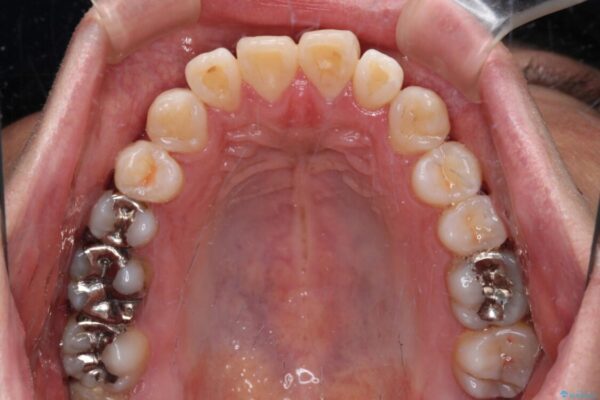

治療後

• 口元の突出感を改善!目立ちにくいワイヤー矯正で自信を持てる自然な横顔に 治療後画像